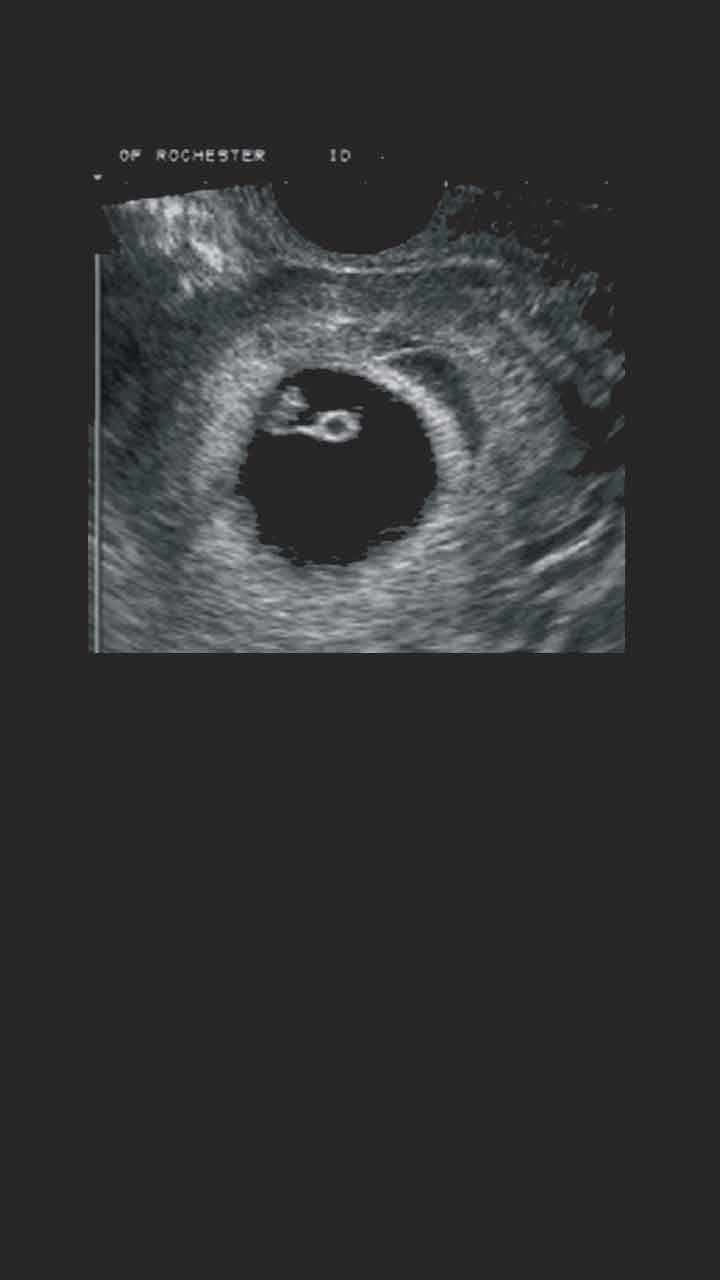

9 Haftalık Gebelik (Hamilelik) Ultrason Görüntüleri

10 hafta yaklaşık 2 buçuk ay süreye işaret eder. 9 haftalık gebelikte henüz bebeğin cinsiyeti belli olmaz. 9 haftalık bebek ultrasonda başı her zamanki gibi göğsüne ve karnına doğru durur.

Ultrasonda Gebelik Kesesi Ne Zaman Görünür? Ay Ay Örnek

9 haftalık bebek ultrasonda başı her zamanki gibi göğsüne ve karnına doğru durur. Gövdesi gelişim halinde olduğundan uzayacak olan bebeğin bağırsakları henüz karnın dışındadır. Anne karnındaki bebeğin cinsiyeti en erken ve en kesin ne zaman belli olur?

Yorum yazmak için üyelik girişi yapmalısınız. Anne kanında fetal dna testi ile 9 haftada cinsiyet anlaşılabilir. 9 haftalik gebeli̇k (hami̇leli̇k) görüntüsü.

9 haftalık bebek ultrasonda başı her zamanki gibi göğsüne ve karnına doğru durur. 9 haftalık hamileyim cinsiyeti ne zaman öğrenebilirim? Yani ana rahmine yerleşmeden önce bebeğin cinsiyeti bellidir.

9 Haftalık Gebelik (Hamilelik) Ultrason Görüntüleri

9 Haftalık Gebelik (Hamilelik) Ultrason Görüntüleri

Bebeğinizin cinsiyetini doktorunuz ultrason ile. 9 haftalık bebek ultrasonda başı her zamanki gibi göğsüne ve karnına doğru durur. 9 haftalık bebek cinsiyeti öğrenilemez, bebeğin dış genital organları henüz oluşmamıştır.